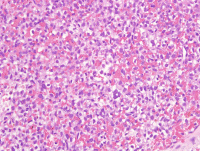

左颊黏膜肿物

性别

女

年龄

63岁

发现左颊黏膜肿物半个月,无明显疼痛

肿物1.5*1.5*1cm,界清,切面实性,红褐色,质软

图1